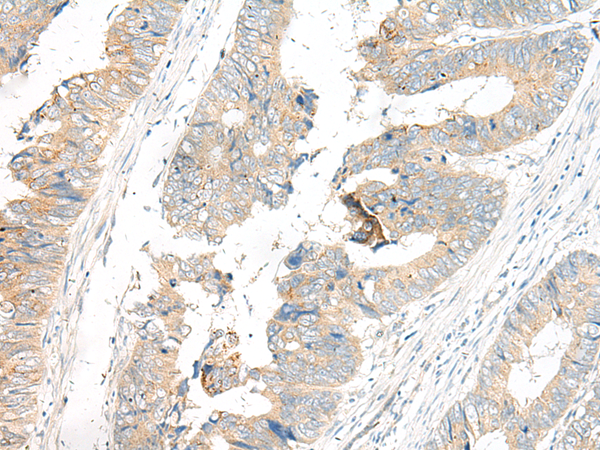

The image is immunohistochemistry of paraffin-embedded Human colorectal cancer tissue using 47582(GP6 Antibody) at dilution 1/50.(Original magnification: 200)